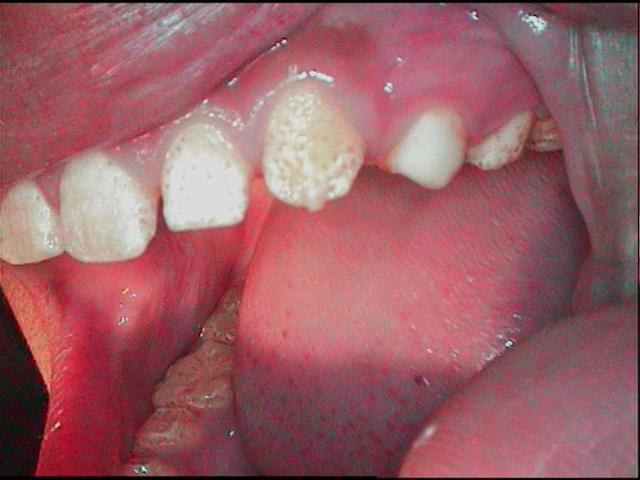

j'ai fait il y a 10jours un test sur 24, grossier! mais pour voir la tolerance

Test prealable sur 24 vv6qwp - Eugenol